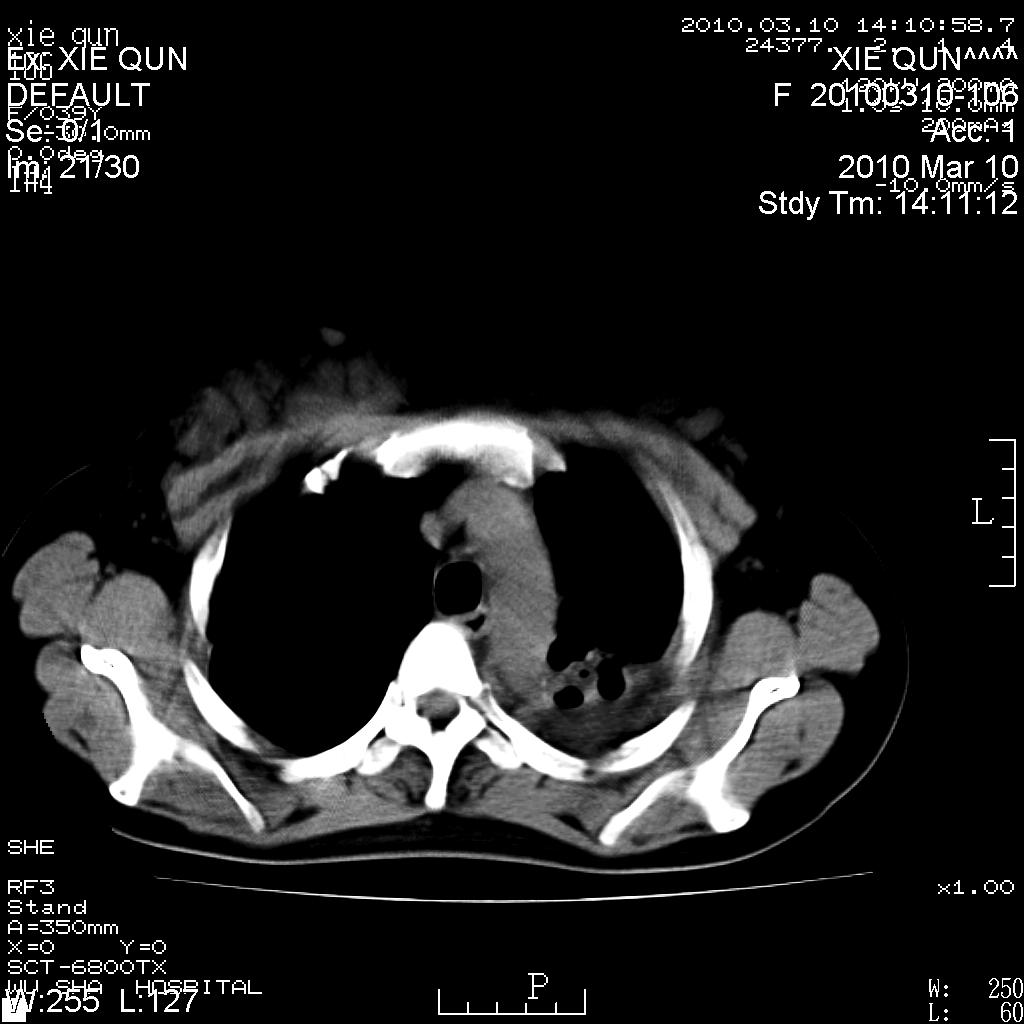

以下是引用心路寻觅在2010-3-24 17:28:00的发言:[br]两肺继发性tb左上肺空洞形成,建议痰检明确诊断。

以下是引用随光逐影在2010-3-24 19:19:00的发言:[br]两肺继发性结核并左上肺上叶空洞形成。